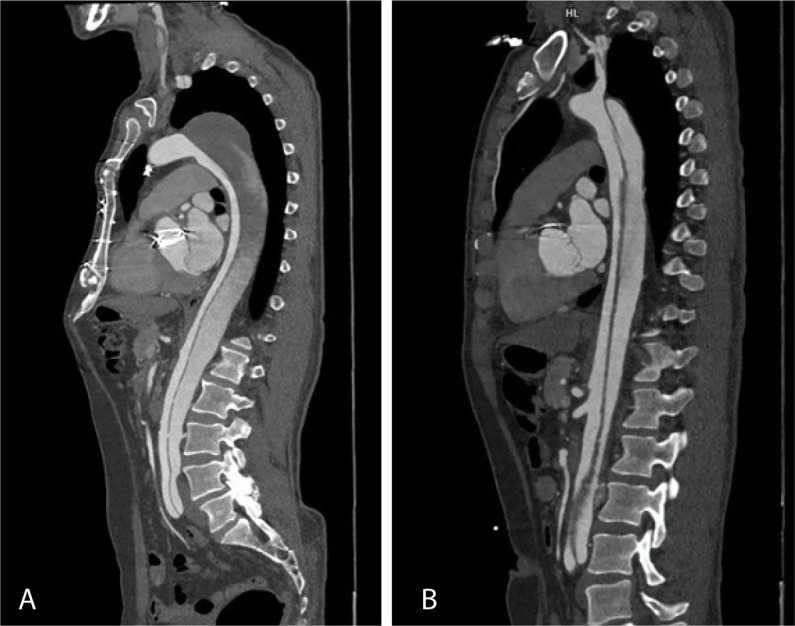

Introduction: Surgical treatment of type A aortic dissection is essentially palliative. Many patients who undergo the procedure still have a dissection flap in the residual aorta, with a persistent patent or partially thrombosed false lumen leaving them susceptible to the dilatation of distal aorta and aneurysm formation.

Methods: Patients who had undergone surgery for type A aortic dissection from January 2015 till December 2022 were recruited into the study. Two follow-up computed tomography scans were performed at least six months apart, the first one at least one month after the surgery.

Results: A persistent dissection flap was found in 34 (68%) patients. All segments of residual distal aorta showed dilatation with time. Growth rate was maximum for abdominal aorta - 3.1 (1.6 - 5.4) mm/year. Patency of false lumen was the only significant factor associated with growth of lower descending thoracic aorta and abdominal aorta (P<0.05). Maximum growth was seen in the patients with partial thrombosis of the false lumen, followed by those with patent false lumen. Two patients with partially thrombosed false lumens required reintervention in the form of endovascular stenting.

Conclusion: Patients after surgery for type A aortic dissection with partially thrombosed false lumens are more prone to aortic dilatation. Regular follow-up of these patients with computed tomography aortogram can lead to timely detection of these sequalae and intervention as needed.